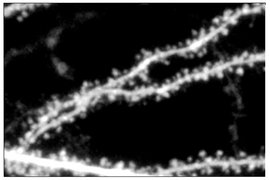

Micrograph showing neural dendrites, where impaired GABA signaling contributes to the observed brain wave alterations in fragile X syndrome.

Further analysis revealed these patterns originate from two subpeaks within the low-frequency band, with the lower subpeak specifically altered in fragile X cases. Through neural circuit experiments in mice, the team traced this biomarker to impaired function of somatostatin-expressing interneurons—inhibitory neurons that shape brain wave patterns via the neurotransmitter GABA.